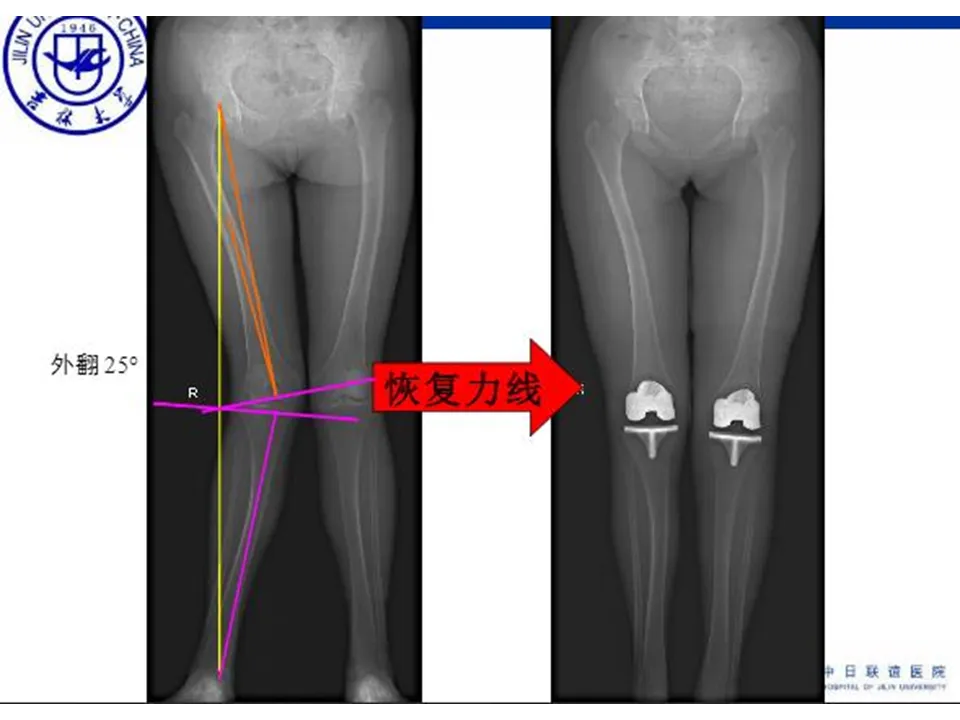

>【骨科PPT】全膝关节置换的截骨原则

【骨科PPT】全膝关节置换的截骨原则